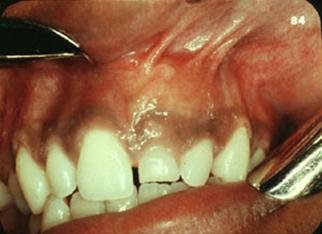

b. Hematom. Chist de eruptie

Mica formatiune localizata pe creasta alveolara, pe mucoasa gingivala, ce apar cu cateva saptamani inaintea aparitiei dintelui respectiv pe suprafata dintelui.

Daca e chist, clinic apare o formatiune mai deschisa, consistenta fluctuenta.

Daca e hematom, apare o secretie seroasa albastruie. In acest caz apar tulburari ale sacului dentar.

Ca localizare, frecvent intalnite la molarii temporari, DAR se pot intalni la orice alt nivel

Nu au semnificatie patologica, se resorb odata cu aparitia dintelui in cavitatea bucala. Daca sunt persistente se face o incizie pentru a usura aparitia dintelui.